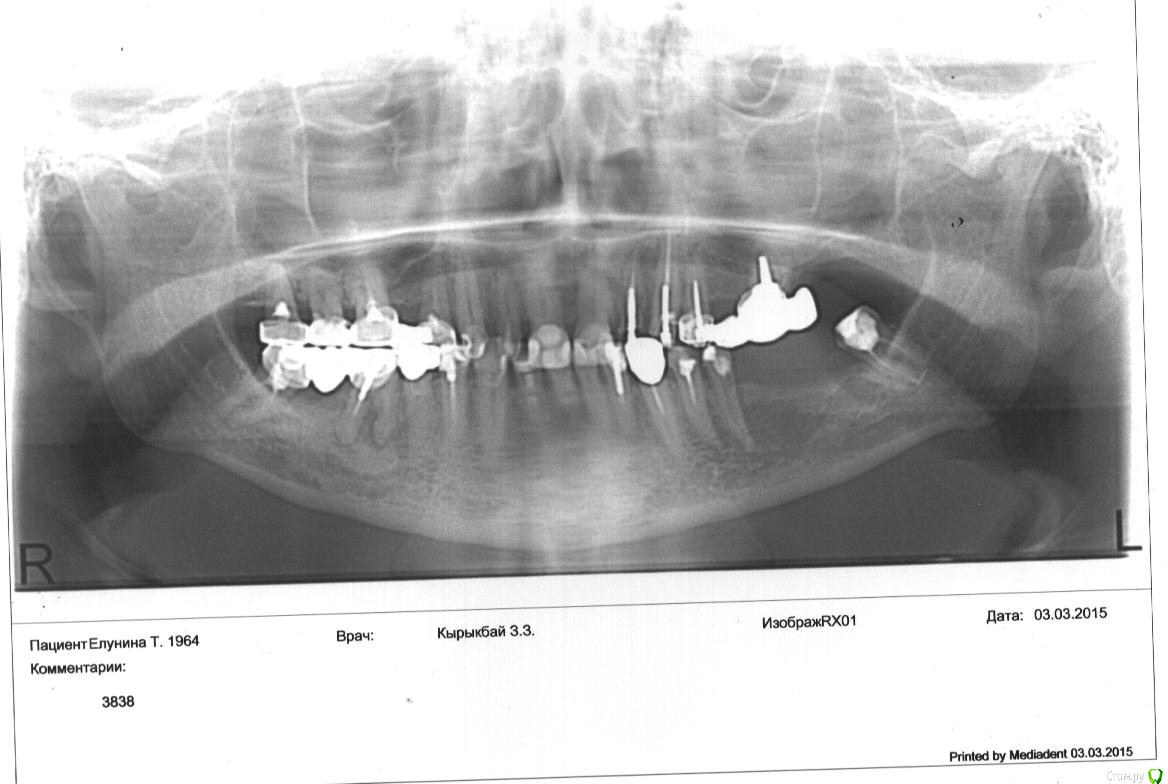

krokomot Опубликовано 15 марта, 2015 Поделиться Опубликовано 15 марта, 2015 А снимка нет? Ссылка на комментарий

Таня64 Опубликовано 16 марта, 2015 Автор Поделиться Опубликовано 16 марта, 2015 Ссылка на комментарий

Таня64 Опубликовано 16 марта, 2015 Автор Поделиться Опубликовано 16 марта, 2015 Я сходила в челюстно-лицевую и врачу сразу сказала, что 8 нижний зуб пломбировала с удалением нерва .Он сказал пройдет,тогда я его спросила, а если не пройдет из за пломбы в канале, и только тогда он предложил сделать снимок панорамный.Я ему принесла этот снимок, он отправил делать снимок одного зуба ( выставлять не буду, там даже корней не видать, так сделали)..Пока я делала этот снимок и принесла ему его, он его даже не посмотрел, сразу отправил на кресло удалять зуб.Я отказалась удалять и с этим снимком бегом к хирургу-стоматологу в стоматологию.Он посмотрел и сказал, что пройдет, раз у вас жжет, распирает, а когда пройдет не сказал.Ну,а врач который мне лечил зуб, поставил на 10 дней временно мостик и сказал, что все пройдет.Так как когда делал укол, у меня по губе разряд прошел. Вообщем зуб мой мне очень нужен, у меня мостик на нем держится((((. Ссылка на комментарий

krokomot Опубликовано 16 марта, 2015 Поделиться Опубликовано 16 марта, 2015 только я не пойму где зуб то лечили слева или справа, и что еще за мостик? На снимке он же стоит или нет? Ссылка на комментарий

diesel87 Опубликовано 16 марта, 2015 Поделиться Опубликовано 16 марта, 2015 Видимо слева, раз пломба в канале) Ссылка на комментарий